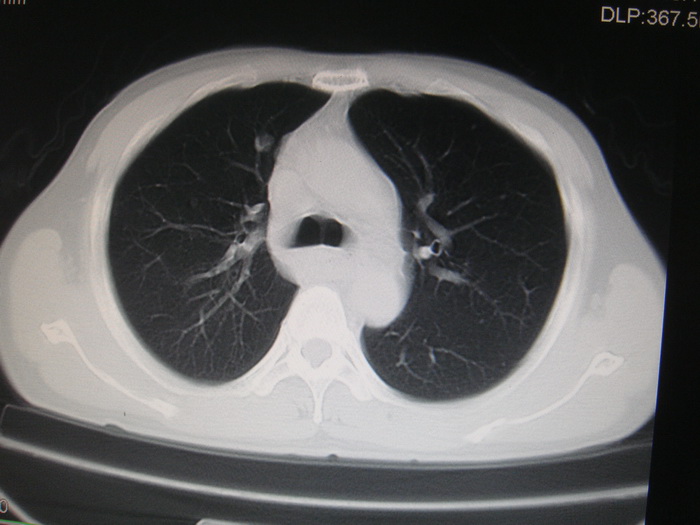

两肺多发结节灶及纵膈淋巴结肿大考虑为转移

两肺多发性转移瘤,纵隔淋巴结转移。

两肺多发性转移瘤,纵隔淋巴结转移。食道中上段管壁似乎增厚,作相关检查。

两肺多发性转移瘤,前上纵隔淋巴结转移。